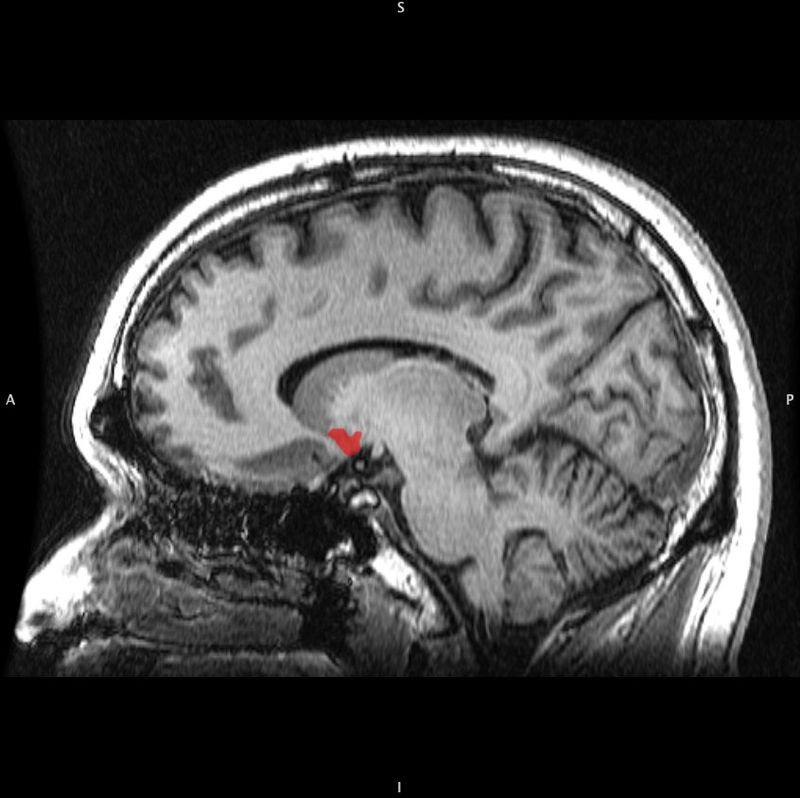

The nucleus accumbens (NAc or NAcc; also known as the accumbens nucleus, or formerly as the nucleus accumbens septi, Latin for “nucleus adjacent to the septum“) is a region in the basal forebrain rostral to the preoptic area of the hypothalamus.

Each cerebral hemisphere has its own nucleus accumbens, which can be divided into two structures: the nucleus accumbens core and the nucleus accumbens shell. These substructures have different morphology and functions.

The nucleus accumbens is an aggregate of neurons which is described as having an outer shell and an inner core.

The nucleus accumbens core (NAcc core) is the inner substructure of the nucleus accumbens.

Location: The nucleus accumbens core is part of the ventral striatum, located within the basal ganglia. Cell types: The core of the NAcc is made up mainly of medium spiny neurons containing mainly D1-type or D2-type dopamine receptors. The D1-type medium spiny neurons mediate reward-related cognitive processes, whereas the D2-type medium spiny neurons mediate aversion-related cognition. The neurons in the core, as compared to the neurons in the shell, have an increased density of dendritic spines, branch segments, and terminal segments. From the core, the neurons project to other sub-cortical areas such as the globus pallidus and the substantia nigra. GABA is one of the main neurotransmitters in the NAcc, and GABA receptors are also abundant.